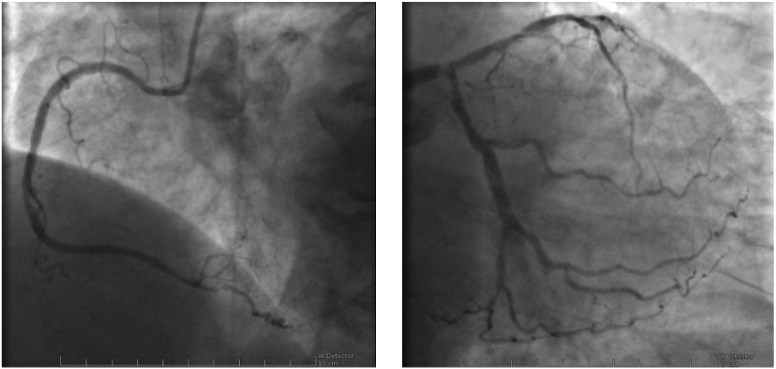

Fig. 1.99mTc-tetrofosmin cardiac SPECT with cadmium, zinc, tellurium (CZT) technology images of a 72-year-old woman with multiple cardiovascular risk factors symptomatic for typical effort angina. Perfusion SPECT revealed a reversible defect in the apex, septal, and anterior walls. Functional data showed an increase in left ventricular end-diastolic volume and end-systolic volume after stress compared to rest (120 versus 114 mL and 80 versus 69 mL, respectively); global systolic function was reduced after stress normal at rest (ejection fraction 40 versus 61%), compatible with myocardial stunning.